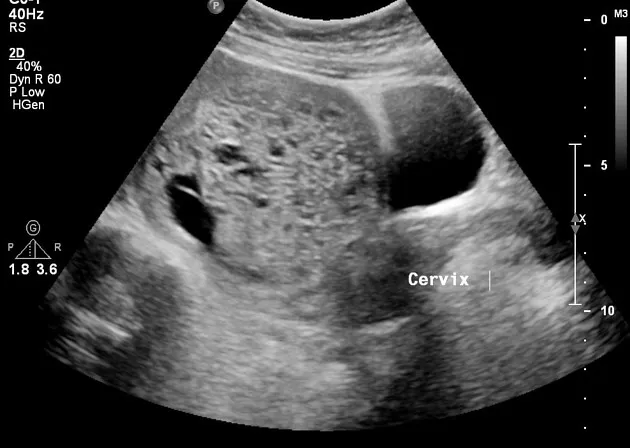

⭐ Complete hydatidiform moles show a classic "snowstorm" or "bunch of grapes" pattern on ultrasound.

- Hydatidiform moles show edematous, avascular chorionic villi ("bunch of grapes").

- Previa: Implants over cervical os → painless bleeding.